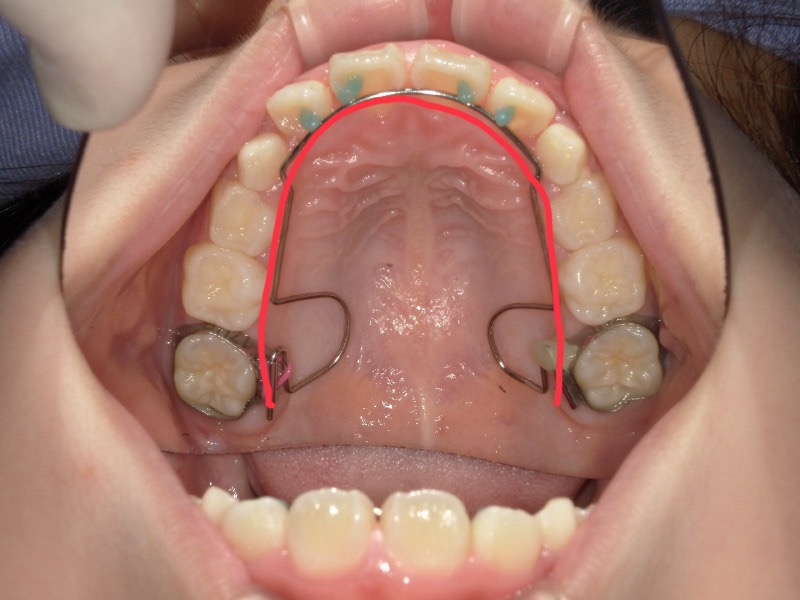

初診の写真を見ると前歯はある程度並んでいますが2番目の歯は斜めに生えており下からの写真では丸いアーチというより平坦のアーチになっています。

これは歯が大きいからよりも顎が小さくスペースが足りていないケースがほとんどです。

スタートから一年後の歯並びです。

初めは平坦気味だった2番目の歯もアーチに沿って綺麗になっています。

ですがまだ生え変わりがあることと、スペースに余裕はないため装置を装着しました。

歯と歯にしっかりと隙間ができて広がっています。

装置をつけると一時的に出っ歯っぽく見えていますがここからまた上顎は変わっていきます。